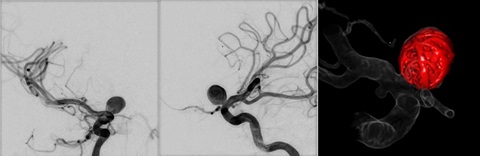

脳血管疾患では脳動脈瘤や短絡疾患に対する塞栓術や、脳梗塞に対する血栓回収療法、頚動脈狭窄症に対する頚動脈ステント留置術などの治療を行っています。短絡疾患では動脈と静脈が複雑に絡み合っているため治療血管を把握することが容易ではありません。そこで高精細な血管の3D画像を血管ごとに色分けして提供することで、医師が治療戦略を考える際の手助けとなり、術中の手技時間の短縮や被ばく低減などにもつながっています。

脳動脈瘤に対するコイル塞栓術(2D血管像(正面・側面)・3D画像(術後))